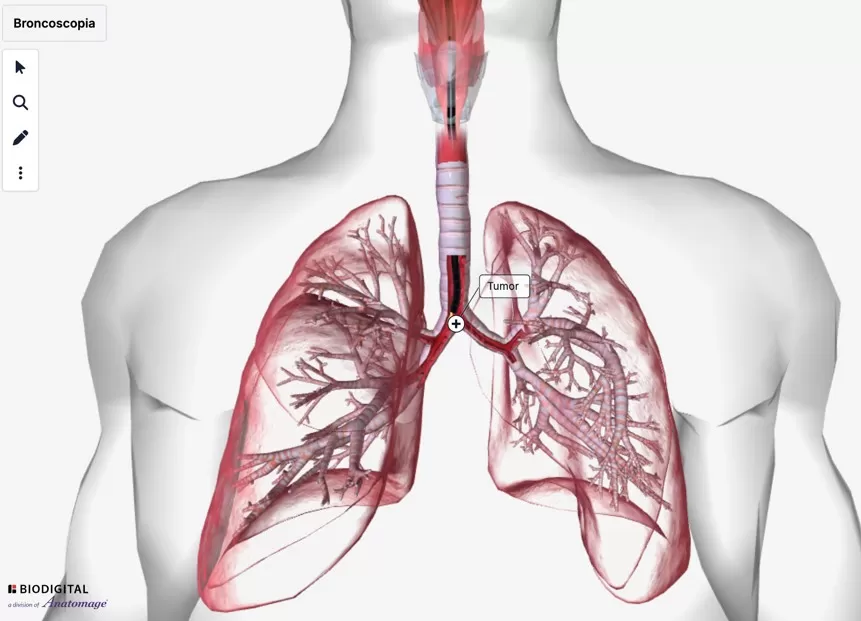

Các bệnh lý có thể hưởng lợi từ công nghệ xạ trị hiện đại trên hệ thống máy gia tốc Elekta Infinity

Xạ trị là phương pháp điều trị sử dụng các tia bức xạ năng lượng cao nhằm tiêu diệt tế bào ung thư. Theo số liệu của Cơ quan Năng lượng Nguyên tử Quốc tế ...